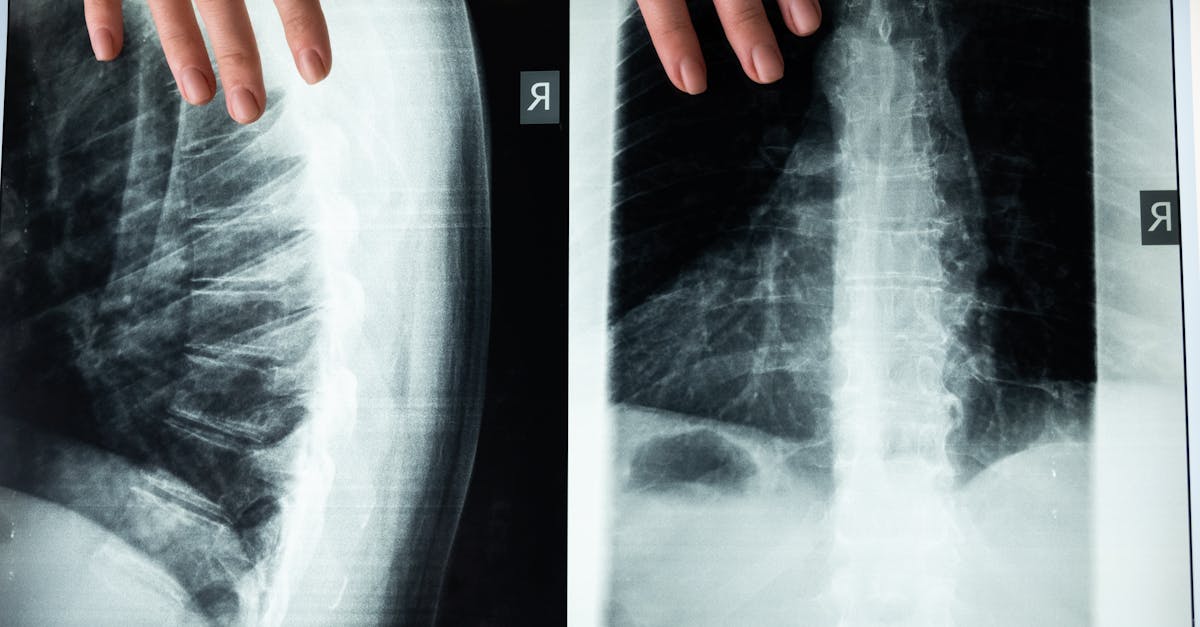

Computed Tomography (CT) scans utilize X-ray technology to create detailed cross-sectional images of the body. During a CT scan, the X-ray machine rotates around the patient, capturing multiple images from different angles. These images are then processed by a computer to generate cross-sectional slices, providing a comprehensive view of the internal structures.

The X-ray beams used in CT scans are absorbed differently by various tissues in the body, producing images with varying degrees of density. Dense tissues like bones appear white on the images, while softer tissues show up as shades of gray. This contrast allows radiologists to distinguish between different types of tissues and identify abnormalities such as tumors or internal injuries. With its ability to visualize structures in great detail, CT scans are valuable tools in diagnosing a wide range of medical conditions.

X-ray based imaging is a widely used diagnostic tool that provides detailed images of the internal structures of the human body. This imaging process involves exposing the body to a small amount of ionizing radiation, which penetrates the tissues and creates a 2-dimensional image on a film or digital sensor. The images produced by X-ray imaging are particularly useful for visualizing bones, teeth, and certain organs such as the lungs.

One of the key advantages of X-ray imaging is its speed and efficiency in capturing images. In a matter of seconds, X-ray scans can provide valuable information to healthcare professionals about the presence of fractures, infections, or abnormalities within the body. Additionally, X-ray imaging is relatively cost-effective compared to other imaging modalities, making it a practical choice for routine diagnostic purposes.